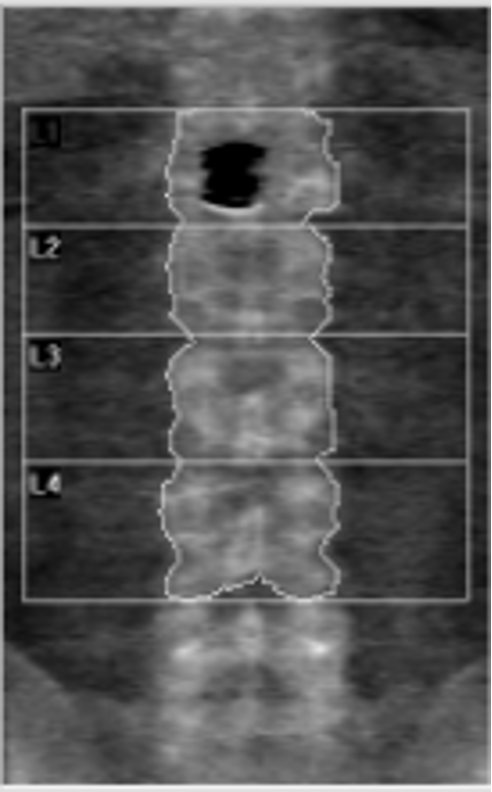

The calcified aorta can clearly be seen overlying this Hologic lumbar spine DXA.

This DXA scan shows aortic calcification, with the accompanying postero-anterior and lateral radiographs showing the aortic calcification. The red lines are point to the aortic calcification. Aortic calcification will tend to overestimate bone mineral density. Aortic calcification is easily appreciated on vertebral fracture assessment (VFA) images. The effect of aortic calcification on bone mineral density has been found to be variable in the literature, however, any authors have found that the additional calcium can increase lumbar spine BMD.